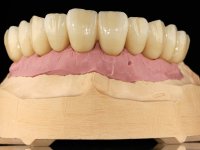

Foi proposto ao paciente fazer uma reabilitação total superior sobre implantes com colocação de uma prótese provisória aparafusada em carga imediata. Após osteointegração seria colocada uma prótese fixa metalo-cerâmica, se possível, com fixação aparafusada. No maxilar inferior foi proposta a colocação de 3 implantes no 4º quadrante para suportar uma ponte metalo-cerâmica de 3 elementos.

Realizada uma TAC, foi planificada a colocação de 6 implantes no maxilar superior. Foi decidida a colocação de dois implantes na zona dos incisivos centrais, dois implantes na zona dos caninos e dois na zona dos segundos pré-molares. A ausência de estrutura óssea na zona distal do primeiro quadrante implicava a realização de uma regeneração óssea no seio maxilar direito. A cirurgia foi realizada e após a colocação dos implantes foi feita a impressão para confeção de uma prótese provisória metalo-acrílica aparafusada para colocação em carga imediata no dia seguinte. O implante colocado na zona do seio maxilar direito não foi colocado em carga. Passados 6 meses foi realizada a impressão aos 6 implantes com técnica de moldeira aberta e foram confecionados os modelos de trabalho. Numa consulta seguinte foram montados os modelos de trabalho em articulador semi-ajustável utilizando o arco facial e a relação inter-maxilar obtida com a prótese provisória. Foi feita uma muralha de silicone sobre a ponte provisória com o objetivo de orientar o trabalho laboratorial. Realizada a infra estrutura metálica aparafusada esta foi provada em boca e finalmente após colocação de cerâmica o trabalho foi colocado definitivamente. Como passaram vários meses após a realização da primeira TAC foi feita uma segunda para planificar a colocação de implantes no 4º quadrante. Colocaram-se 3 implantes na mesma sessão em que foi feita a extração dos pilares da ponte. Estes implantes foram posteriormente reabilitados com uma ponte metalo-cerâmica aparafusada de três elementos.